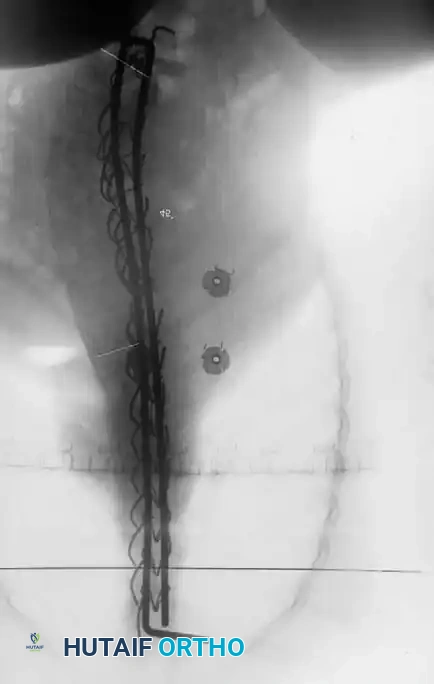

3. Instrumentation Strategies

Due to poor bone stock, multiple points of fixation are required to distribute corrective forces.

* Segmental Instrumentation: The gold standard involves rigid rod constructs (e.g., Cotrel-Dubousset principles) utilizing pedicle screws, hooks, and sublaminar wires or cables.

* Sublaminar Wires/Cables: Techniques pioneered by Luque remain highly relevant in neuromuscular scoliosis. Sublaminar cables provide excellent pull-out strength in osteopenic bone and distribute translational forces evenly across the apex of the deformity.

Associated Surgical & Radiographic Imaging

Hutaifortho's Orthopaedic Diagram